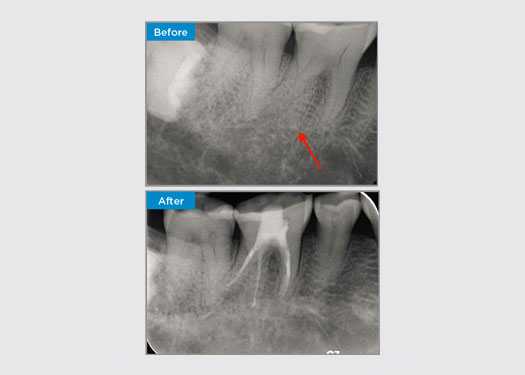

Le patient s’est présenté avec une pulpite irréversible sur la dent 46. Sur la radiographie préopératoire, la dent 46 présente une racine distale supplémentaire (morphologie de la dent Radix Entromolaris). Un balayage CBCT a confirmé la présence d’une racine DL avec une courbure radiculaire sévère. Une sélection minutieuse des limes est essentielle pour cette racine DB délicate.

Dr Jack Lin, Endodontiste, Sydney, NSW Australie